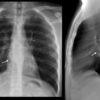

Lao hạch

Lao hạch - Ảnh 2

Lao hạch - Ảnh 3

Lao hạch - Ảnh 4

» Thông tin: Nam giới – 27 tuổi.

» Lâm sàng: Đau ngực / Nuốt khó.